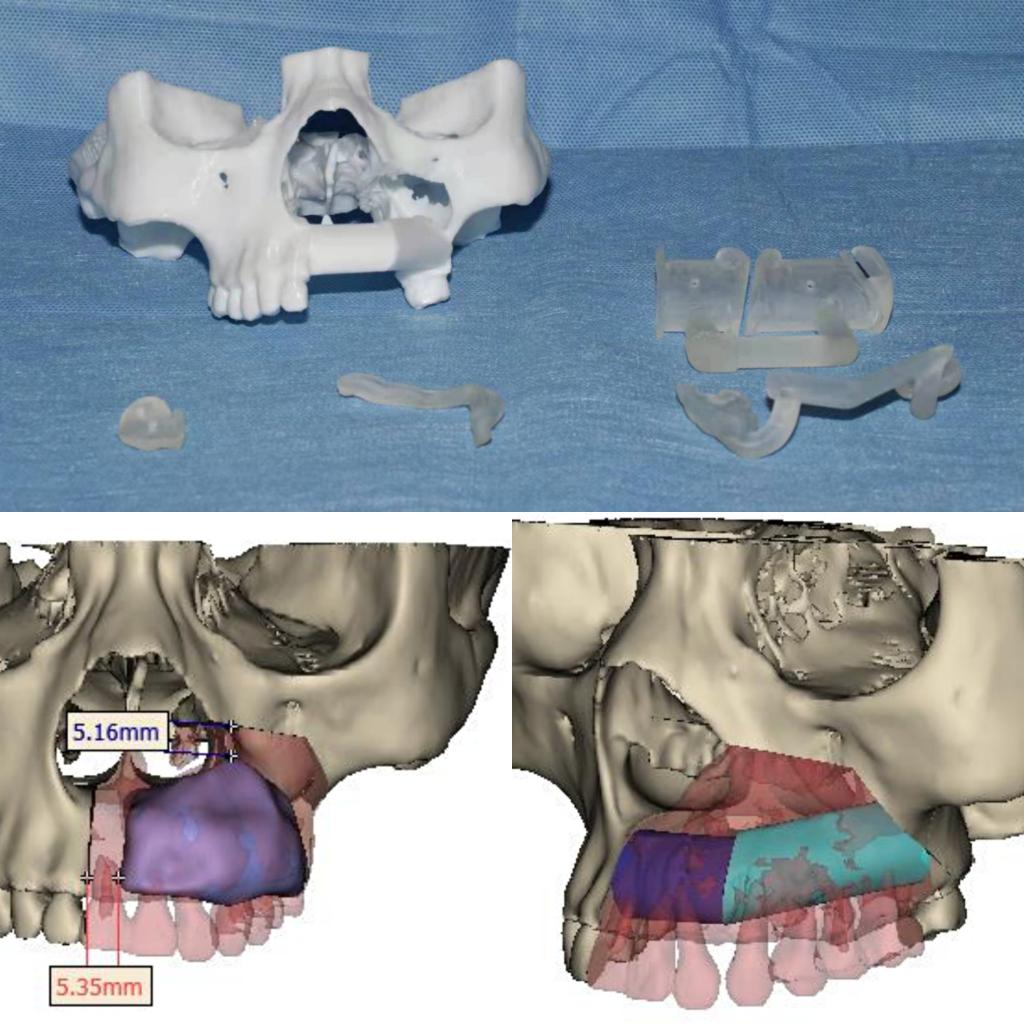

患者今年25岁,是一名年轻的母亲,1年前左侧上颌牙龈出现无痛性肿块,肿块逐渐增大,导致左侧面部畸形和牙松动。心急如焚的她咨询多家医院后,就诊口腔医院口腔颌面外科,口腔颌面外科主任吴亚东了解其病情后,制定了详细完善的个性化手术治疗方案,用血管化腓骨移植修复左侧上颌骨肿瘤切除后的缺损,既保证了术后不会因为硬组织缺失而导致面部塌陷,也能为后期种植牙修复提供足够的骨量。由于患者为年轻女性,为避免在面部留下明显的瘢痕,手术没有行上唇正中至鼻旁入路或下唇侧唇劈开入路,病灶切除及腓骨就位均在口腔内切口完成,但这也大大增加了手术难度。

本次手术历时6个小时,吴亚东团队精确切除了患者左上颌骨肿瘤,利用数字化血管化腓骨瓣及个性化钛网重新恢复了这位年轻妈妈的面型及上颌骨缺损。术后在口腔颌面外科护理团队的精心护理下,患者病情恢复良好,现已治愈出院。面型基本对称,移植的腓骨瓣存活良好。半年后,这位年轻的妈妈就可以利用“新的上颌牙槽嵴”进行种植牙恢复咀嚼功能。

目前,口腔医院完成血管化骨瓣移植修复重建下颌骨、血管化肌皮瓣修复软组织缺损已超百例,技术成熟,各类骨肌皮瓣存活率极高。但上颌骨肿瘤因临近鼻腔、上颌窦、眼眶等重要复杂结构,缺损的形态不规则,切除后缺损的修复有极大难度。上颌骨切除术后会导致口鼻瘘、面型畸形、语言及进食障碍、甚至对病人及其家属造成巨大的心理障碍。口腔颌面外科致力于解决患者的病痛,利用计算机辅助设计 / 计算机辅助制造(computer assisted design/computer assisted manufacture,CAD/ CAM),精准切除肿瘤及修复上颌骨缺损。术前设计、术中准确控制以及术后可靠预测,手术可获得理想上颌骨重建效果。在满足患者外形需求的同时,还保障了相关功能,真正做到了个性化功能性修复重建。